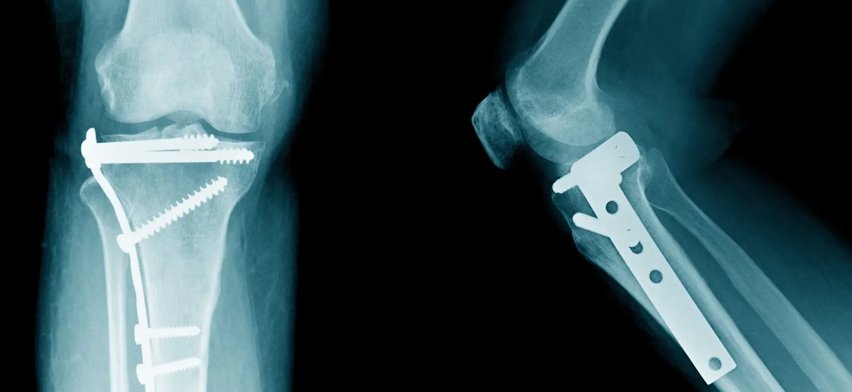

Fracture fixation is a surgical procedure used to stabilize and heal broken bones. When a bone breaks due to trauma, accident, fall, or sports injury, proper alignment and stabilization are essential for optimal healing. Fracture fixation uses plates, screws, rods, nails, and external fixation devices to hold bone fragments in the correct position until healing is complete.

• Internal Fixation – Plates, screws, intramedullary nails

We begin with a detailed orthopedic evaluation, including X-rays and advanced imaging to map the fracture pattern and develop a precise surgical plan.

Using modern orthopedic implants and trauma fixation tools, we ensure: